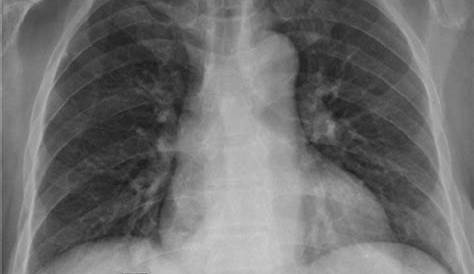

Тонкие иглы аспирации массы интерпретировались как меланома. При чтении простой рентгенографии грудной клетки следует специально смотреть на спинномозговые элементы, включая параспинальные линии и мягкие ткани, как на боковой, так и на лобной перспективе. Наиболее распространенные параспинальные доброкачественные новообразования включают липомы, фибробластные опухоли и доброкачественные опухоли периферической нервной оболочки. Фраза «мягкие ткани незаметны» играет значительную роль в описании состояния определенных структур тела.

Непримечательно в медицинских терминах означает нормальный.Привет ~ это означает, что есть некоторые необычные кальцифи-изображения, выявленные экстраплевральной параспинальной массой в области t8. Эти критерии должны помочь в решении, требуется ли дальнейшая визуализация, когда сомнительные аномалии встречаются на лобных рентгенограммах грудной клетки.

Вместо того, чтобы фокусировать глаза только на внутриспинальных структурах или костном позвоночнике (туннельное зрение), радиологи должны тщательно изучить все серии изображений для поражений в паравертебральных мягких тканях и даже за их пределами, таких как ретроперитонум, легкие и мягкие ткани. Привет, что конкретно означает дистрофическая оссификация задних параспинальных мягких тканей? (а, b) обнаружение параспинальной массы на рентгенографии. Диагноз многих таких поражений может быть сделан с легкостью, особенно когда он коррелирует с клиническими и радиологическими результатами.

Рентгенография грудной клетки показывает аномальную правую параспинальную мягкую ткань